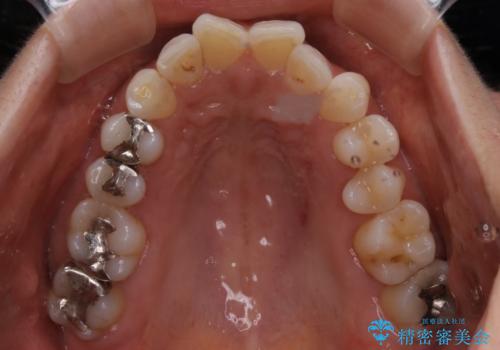

診断の結果、一番奥の歯は失活していたため精密根管治療から治療介入となりました。奥から2番目の歯にも大きな虫歯が認められたため、セラミックインレーによる補綴治療を行いました。 精密根管治療は患者様のご希望により、福本院長に行っていただきました。

根管治療をした歯は神経のある歯と比較して強度が下がり、長期的に破折のリスクが高まると言われています。破折のリスクを軽減させるため、根管治療を行った歯に対しては歯冠をすべて覆うクラウンという被せ物にて補綴処置を行います。

適合不良の補綴物は二次的な虫歯発生のリスクが高まります。

自費診療で用いられる材料は保険適応の材料に比べて、より精密で適合の良い被せ物作ることができるため、長期的な虫歯のリスクを大幅に減らすことが可能です。

今後は他の銀歯のやり替えも順次行っていくこととなりました。